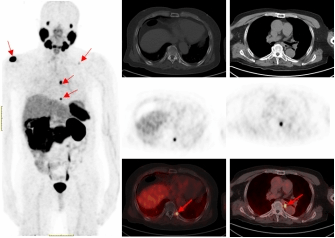

一名75的岁男性患者自2019年确诊前列腺癌后,先后接受过两次内分泌治疗及前列腺癌根治术的综合治疗。在术后两年的复查中发现血PSA持续升高,CT检查和全身骨显像检查均未发现明显异常,医生建议随诊,患者来到桃花视频

附属医院要求进一步检查。经核医学科68Ga-PSMA PET/CT检查后结果显示,双侧肩胛骨、左侧第9后肋、第2腰椎及纵隔淋巴结均已存在癌症转移。